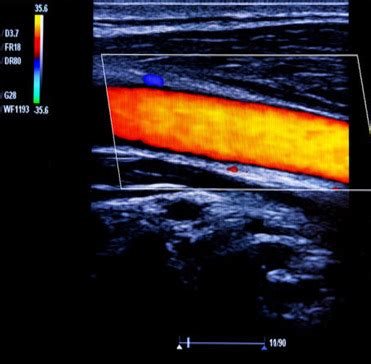

Now, let’s talk about the star of the show: how Doppler ultrasound specifically helps us spot Deep Vein Thrombosis (DVT). DVT occurs when a blood clot, usually in a deep vein of the legs, blocks blood flow. This is serious business, as the clot can break off and travel to the lungs, causing a pulmonary embolism (PE), which is a life-threatening condition. Doppler ultrasound is the gold standard for diagnosing DVT because it can directly visualize these clots and, crucially, assess the impact on blood flow. The procedure typically involves a trained sonographer applying a gel to your skin over the suspected area (usually the legs) and then moving a transducer, a handheld device, over the skin. This transducer emits high-frequency sound waves. As these waves travel through your body, they bounce off various tissues and structures, including your blood vessels and the red blood cells within them. The machine listens to the returning echoes. In areas without a clot, the sound waves will reflect off the moving blood cells predictably, showing a normal flow pattern. However, when a clot is present, it can partially or completely block the vein. This blockage will alter the sound wave reflections in several ways:

1. Direct Visualization of the Clot: In many cases, the clot itself can be seen as an echogenic (bright) material within the vein, obstructing the normal lumen (the open space where blood flows). The sonographer looks for a lack of compressibility of the vein; a healthy vein will flatten when gentle pressure is applied by the transducer, but a vein filled with a clot will remain rounded.

2. Altered Blood Flow Patterns: This is where the ‘Doppler’ part really shines. The machine detects changes in the frequency of the returning sound waves. If blood flow is reduced or absent in a segment of the vein due to a clot, the Doppler signals will be weaker or absent altogether. The sonographer will assess ‘phasicity’ (the normal rhythmic changes in blood flow related to breathing) and ‘compressibility’ of the veins. A clot disrupts these normal flow characteristics.

By combining these findings—visualizing the clot, assessing compressibility, and analyzing the Doppler signals for flow abnormalities—doctors can confidently diagnose DVT. It’s a powerful tool because it provides real-time information about the health of your venous system, helping to guide treatment decisions and prevent serious complications.